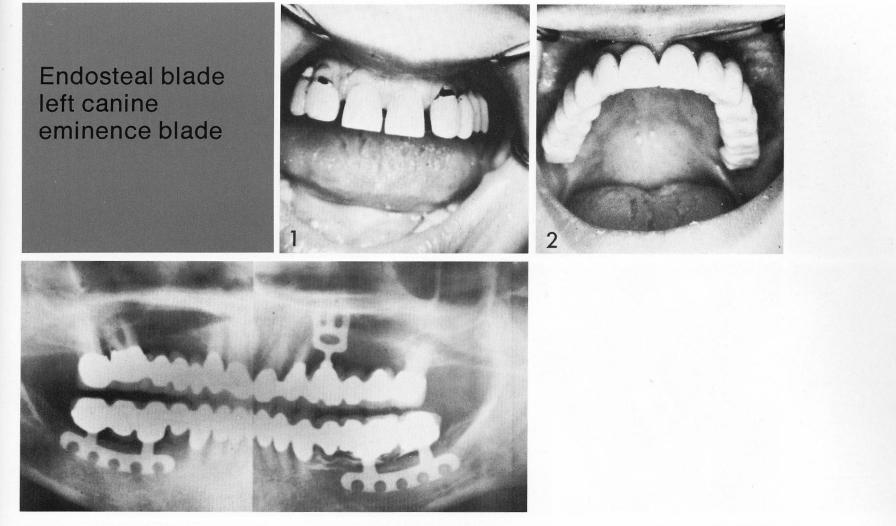

The remaining teeth were not attractive (I), an upsetting characteristic to the cosmetically conscious patient. To bolster abutment support, a bladevent was inserted in the cuspid area. The final restoration (2) is a distinct improvement over the previous situation.

1 The maxillary bladevent implant inserted in the cuspid area